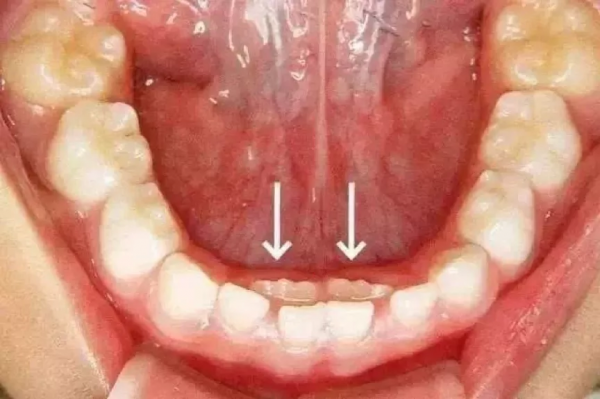

有的孩子長了雙排牙,家人也遲遲沒發現;

雙排牙。圖片來源:蘇州口腔醫院

有不少家長,就是因為不關注換牙順序,平時也不檢查孩子口腔,等到雙排牙長出好一段時間了才發現,然後急匆匆地帶孩子去醫院拔牙……

有不少家長,特意把孩子的食物切得很碎,方便孩子吞嚥。然而,吃得太精細反而不利於牙齒髮育,孩子的咀嚼功能得不到鍛鍊,更容易出現雙排牙和齲齒問題。